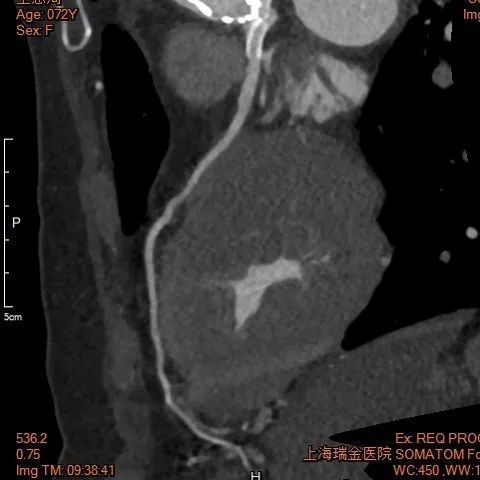

主动脉

右股

左股

术后1w——冠脉CTA